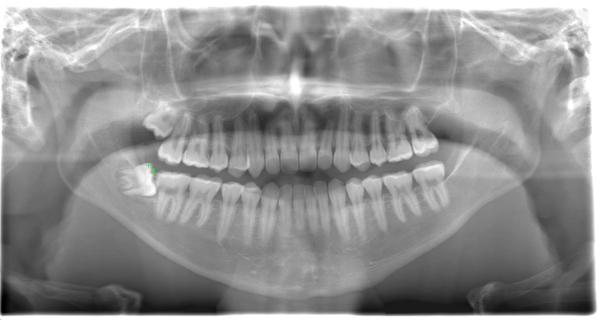

CASE 3

| 年齢・性別 | 20代・男性 |

| 主訴 | 左下親知らず抜きたい |

| 親知らずのはえ方 | 半埋伏 |

| 抜歯期間 | 30分 |

| 抜歯費用 | 約2,500円(保険内) 別途CT撮影で3,000円 |

| 抜歯内容 | 左下の半埋伏親知らず抜歯 |